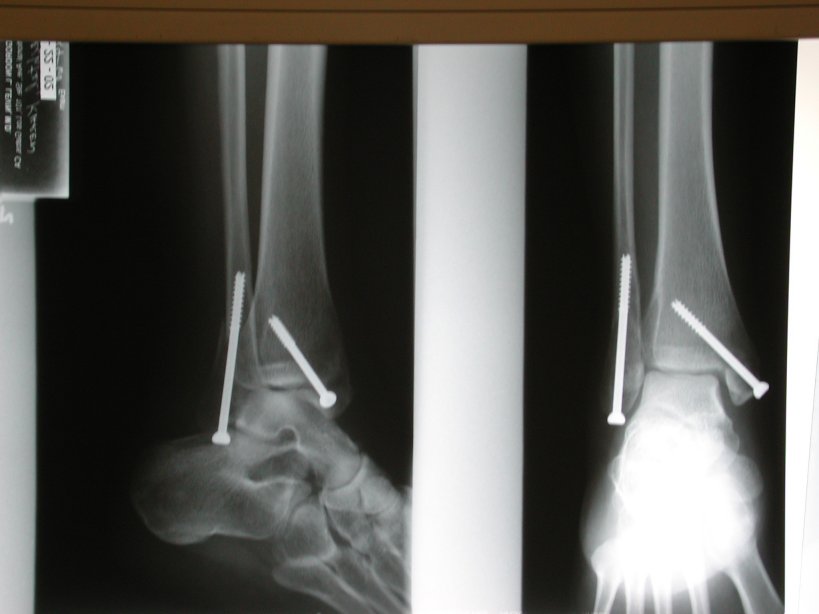

Updated X-Rays (1)

Updated X-Rays (2)

Updated X-Rays.